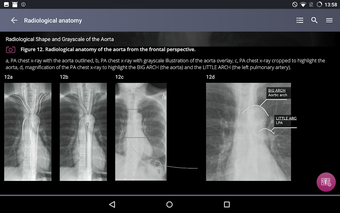

Radioloji'yi Keşfet: Göğüs Röntgeni Yorumlama, göğüs röntgeninin yorumlanmasının anlaşılmasını artırmak için tasarlanmış bir eğitim uygulamasıdır ve doktorlar, tıp öğrencileri ve radyologlar tarafından kullanılması amaçlanmaktadır. Uygulama, en küçük detayları görüntülemek için yakınlaştırılabilecek yüksek kaliteli görüntüler ve her bulgunun önemini anlamanıza yardımcı olacak bir sesli yorum içerir.

Uygulamanın amacı, kullanıcıların farklı x-ışını bulgularını ve bunların bir hastalığın teşhisinde nasıl kullanılabileceğini daha iyi anlamalarına yardımcı olmaktır. Uygulama, göğüs röntgeni yorumlaması için gerekli çeşitli yapı taşlarını kapsayan 5 bölüme ayrılmıştır.